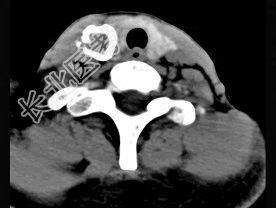

- 多项选择题50岁女性患者,体检发现右侧甲状腺有较硬结节, CT扫描如图所示,请选择正确的描述和答案 ( )

A、右侧甲状腺内见稍低密度影,周边围以环形致密钙化影

B、肿块影与周围结构分界清楚

C、考虑为结节性甲状腺肿

D、考虑为甲状腺癌

E、考虑为甲状腺腺瘤钙化